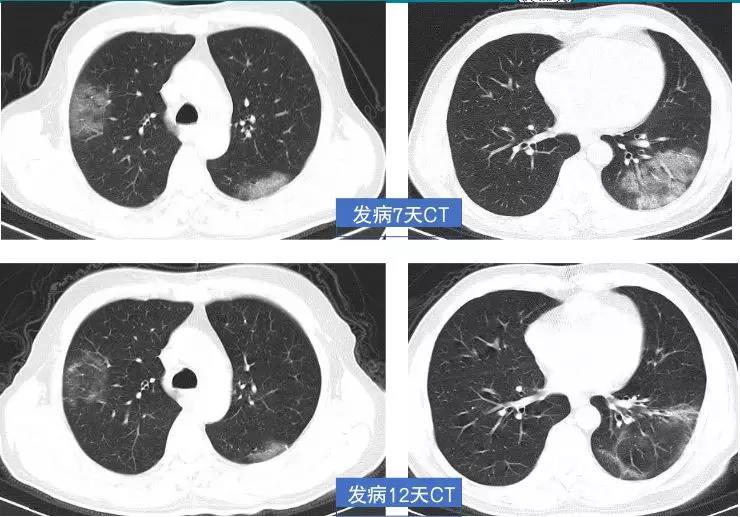

新型冠状病毒感染的肺炎CT图像

新型冠状病毒感染的肺炎CT图像

新型冠状病毒感染的肺炎治疗前后CT图像对比

1、检出率高:因新冠肺炎影像表现早于临床,因此影像学检查是临床前期筛查具有不可替代的作用。

2、快速评估治疗疗效:在临床治疗中, 进行CT检查, 有利于准确判断肺部病变类型、程度、范围以及变化情况。

3、为治愈及出院主要指标之一:核酸阴性CT阳性患者或需要继续留观。

李云启介绍,新型冠状病毒肺炎早期呈现多发小斑片影,以及间质小条索状改变,以肺外带明显。进而发展为双肺多发磨玻璃影、浸润影及网格状纤维化改变。严重者可出现肺实变,甚至机化样改变。虽然肺部CT可能出现“同影异病”的情况,也不能作为核酸检测的替代品确诊新型冠状病毒肺炎,但面对核酸检测条件不允许、疑似病例难以确诊的状态,CT 检查可作为强有力的补充手段进行查漏补缺、防微杜渐,从而尽快找到更多疑似病例和密切接触者进行隔离。寿光市中医医院影像中心拥有全球领先的美国GE公司生产的512层Revolution CT,GE Revolution CT作为美国全进口超高端医疗影像设备,具有扫描速度快、辐射剂量低、图像质量高等多方面等特点,尤其是在肺部扫描、心脏冠状动脉及全身血管联合成像上有无可比拟的优势。